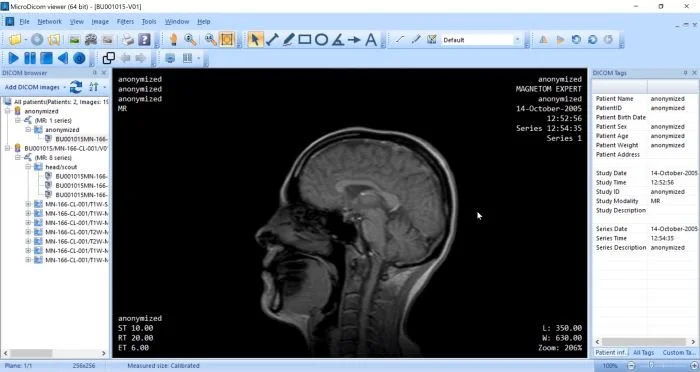

Популярные программы для просмотра DICOM-файлов (Windows, macOS, iOS, Android и Linux)

Видео-обзор лучших программ для просмотра DICOM-файлов